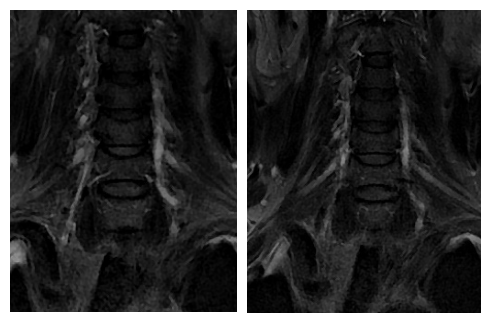

神经内科张桂莲教授带领介入团队在影像科李晓会教授团队鼎力支持下,反复查阅相关文献,尝试多种新型磁共振成像技术,最终历时4个小时,克服了肺内气体对磁共振成像质量的影响,通过特殊的MRI成像技术及体表定位技术,清晰显示出脑血管造影及高分辨核磁共振不能显示的闭塞的椎动脉开口,使之前无法完成的高难度手术变成可能。

最终,在患者入院第4天,张桂莲教授带领的介入团队选择局麻条件下为患者成功实施了神经介入领域的高难度手术—左侧无残端椎动脉长节段慢性闭塞再通术。因术前清晰的影像显影及准确的体外定位标记,左侧优势椎动脉顺利开通,手术耗时仅仅约90分钟。术中及术后患者配合良好,无任何不适,术后在介入准备室,张桂莲教授向患者女儿详细告知手术过程及患者目前状况,患者女儿喜极而泣,多次向介入团队表示感谢。